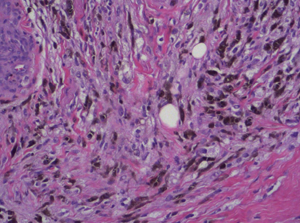

Soft-Tissue-Sarcoma

Soft Tissue Sarcoma